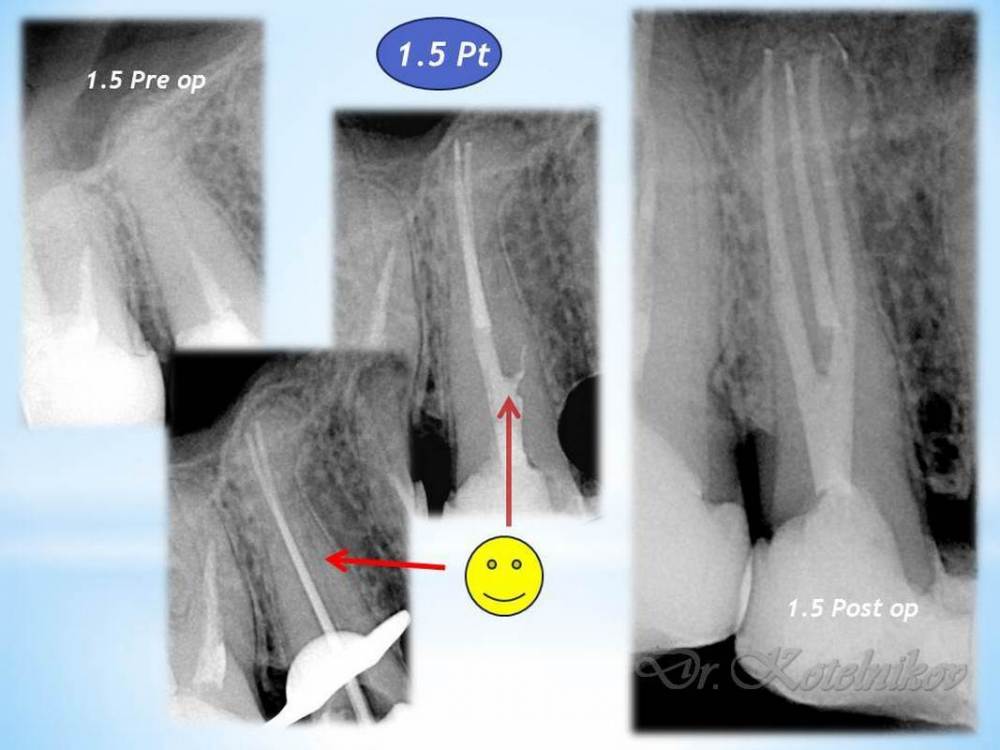

Ico Опубликовано 10 апреля, 2022 Автор Поделиться Опубликовано 10 апреля, 2022 (изменено) 3 отдельных канала в нижнем премоляре,паковка похожая как у Томаса Ланга.Каллибровка,паковка апексов была по S2 протейперу + 25 к. Изменено 10 апреля, 2022 пользователем Ico 1 1 2 Ссылка на комментарий